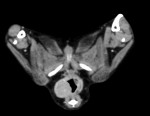

次いで手術の是非と可否を検討するためCT検査を実施した結果、附属リンパ節や肝臓、肺などへの転移は認められなかったため、一部の直腸と一部の肛門括約筋を含めて腫瘍を摘出した。